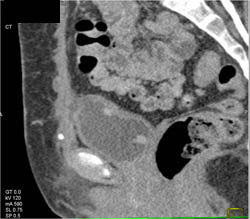

Bladder Cancer